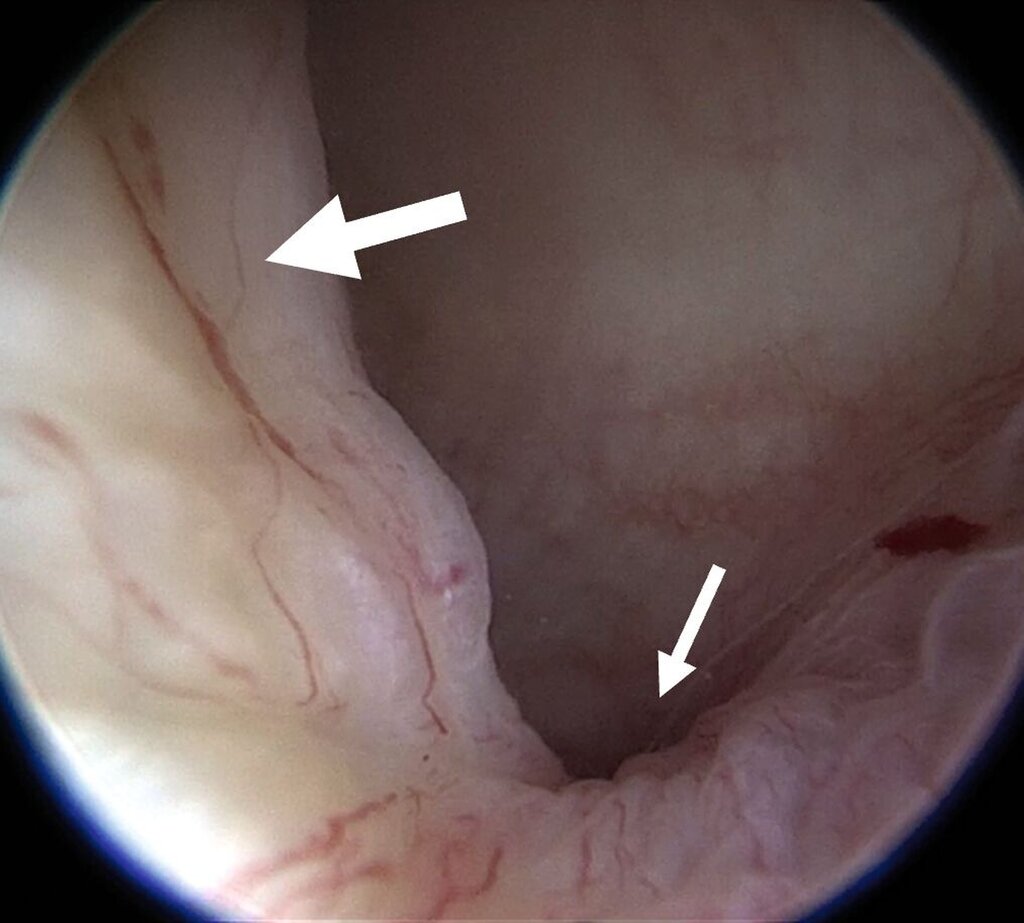

Für die Kiefergelenksarthroskopie ist eine strukturierte Orientierung innerhalb des oberen Gelenkkompartiments essenziell. Hierfür haben sich die sogenannten „seven points of interest“ nach McCain etabliert (Abbildung 3) [Srouji et al., 2018]. Diese sieben anatomischen Referenzpunkte dienen der systematischen Beurteilung des Gelenks während des arthroskopischen Eingriffs. Zunächst werden das mediale synoviale Band und der Pterygoid-Schatten („pterygoid-shadow“) als Orientierungspunkte identifiziert. Es folgen die bilaminäre Zone – eine häufige Schmerzquelle – sowie die hintere Schräge der Gelenkeminenz. Die Beurteilung des Discus articularis gibt Auskunft über Verlagerungen und degenerative Prozesse. Es folgt die Beurteilung der intermediären Zone, die besonders anfällig für eine Perforation ist. Abschließend erfolgt die Begutachtung des vorderen Recessus. Dieser stellt den Eintritt der Punktionsstelle des Level-II-Zugangs dar [Srouji et al., 2018].

Die Level-II- (Abbildung 4a) beziehungsweisedie Level-III-Arthroskopie beinhalten zusätzlich einen zweiten beziehungsweise einen dritten Zugang über den beispielsweise Verwachsungen entfernt (Abbildung 4b) oder auch Biopsien entnommen werden können. Darüber hinaus ermöglichen diese die Durchführung eines sogenannten „anterior release“ (Abbildung 5). Darunter versteht man das arthroskopische Durchtrennen des vorderen Aufhängungsbandes des Diskus, wodurch dessen Beweglichkeit verbessert werden kann. Auf diese Weise kann der Diskus (unter anschließender konservativer Therapie) wieder in eine physiologischere Position zurückgleiten. Darüber hinaus können auch weiterführende Eingriffe wie Diskopexien durchgeführt werden, also die arthroskopisch gestützte Reposition und Fixation des Diskus in anatomisch korrekter Position [McCain, 1988].